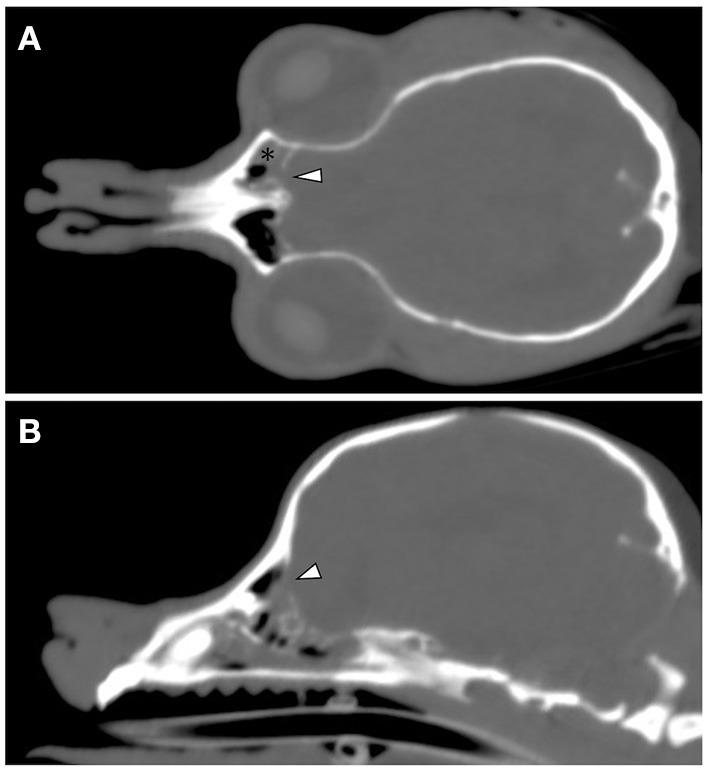

A 12-year-old Yorkshire terrier was referred for epileptic seizures and nasal discharge. The fluid was clear and serous. Cerebrospinal fluid (CSF) rhinorrhea was suspected, based on clinical signs and MRI findings. In humans, analysis of nasal secretions to determine the concentration of glucose and brain-type transferrin has been widely used clinically in order to confirm the presence of CSF rhinorrhea. The glucose concentration in the nasal discharge was 74 mg/dL. Serum-type and brain-type isoforms of transferrin were detectable in the nasal sample. The concentration of glucose and brain-type transferrin could be useful for diagnosing CSF rhinorrhea.

一只12岁的约克夏梗因癫痫发作和鼻分泌物增多前来就诊。分泌物清澈且呈浆液性。根据临床症状和磁共振成像(MRI)结果,怀疑存在脑脊液鼻漏。在人类中,分析鼻分泌物以测定葡萄糖和脑型转铁蛋白的浓度已在临床上广泛用于确认脑脊液鼻漏的存在。鼻分泌物中的葡萄糖浓度为74毫克/分升。在鼻样本中可检测到转铁蛋白的血清型和脑型异构体。葡萄糖和脑型转铁蛋白的浓度可能有助于诊断脑脊液鼻漏。